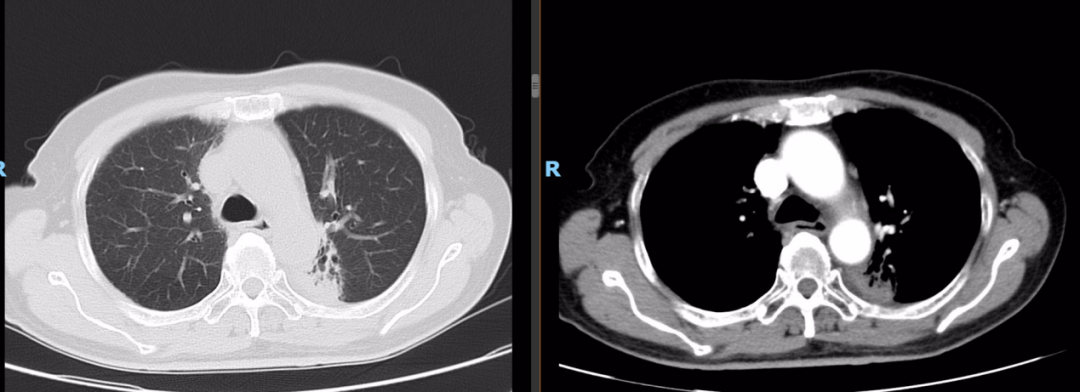

PET-CT(2020-08-13):食管胸下段管壁不均匀增厚,见放射性摄取增高,大小约18×14×27mm,SUVmax 14.6,符合食道癌表现。右侧肺门及纵隔(4R、5、7区)可见多个稍肿大淋巴结,最大约8×5mm,考虑炎性淋巴结可能性大。

左肺上叶尖后段团块状密度增高影,PET见放射性摄取增高,大小约40×29×31mm,SUVmax 28.0。病灶跨越左侧斜裂胸膜生长,密度均匀。左肺上叶胸膜下可见多发微小结节状密度增高影。建议治疗后复查,必要时活检排外恶性肿瘤的可能。

胸部平扫+增强CT(2020-08-27):食道中段管壁增厚,上下累及约4.5厘米(约胸5/6椎间隙水平至胸8椎体上缘水平),增强后可见轻度强化,隆突下见境界不清淋巴结。左肺上叶尖后段及相邻左肺下叶背段交界处见团块状直径约2.5厘米软组织密度灶,边缘可见毛刺,左侧胸腔积液,左下肺膨胀不全。右肺下叶见少许条状影。结论:1、食管癌。2、左肺上叶尖后段病灶,符合肺癌。左侧胸腔积液,左下肺膨胀不全。

2021-10-28外院PET-CT:原食管胸下段管壁高代谢灶较前缩小,放射性较前减低,现大小约15×17×17mm,SUVmax 3.1,考虑为治疗后改变。左肺上叶团块状高代谢灶较前缩小,放射性摄取较前减低,现大小约25×18mm,SUVmax 2.1,考虑为治疗后改变。

2022-03-28 PET-CT:1、食管癌放化疗后,食管胸中段管壁不规则增厚伴结节状代谢增高,与上次(2021-10-28)PET/CT检查对比,病灶代谢较前明显增高,考虑为肿瘤复发病灶。2、左肺癌放疗后及靶向药治疗后,原左肺上叶团块状高代谢“肿瘤灶”,现范围较前稍缩小,代谢较前稍减低,考虑为治疗后改变(肿瘤完全活性受抑,伴少许炎性反应可能)。